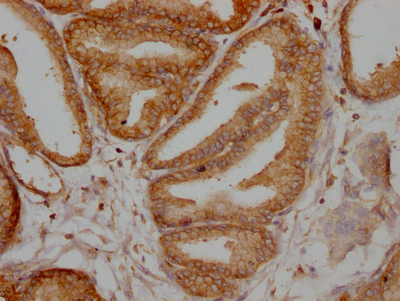

IHC image of CSB-RA214107A0HU diluted at 1:100 and staining in paraffin-embedded human prostate tissue performed on a Leica BondTM system. After dewaxing and hydration, antigen retrieval was mediated by high pressure in a citrate buffer (pH 6.0). Section was blocked with 10% normal goat serum 30min at RT. Then primary antibody (1% BSA) was incubated at 4℃ overnight. The primary is detected by a Goat anti-rabbit IgG polymer labeled by HRP and visualized using 0.05% DAB.